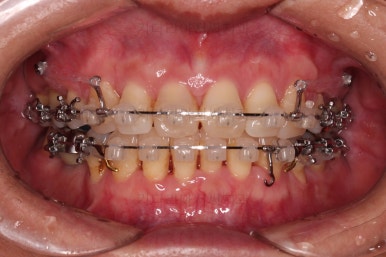

동래임플란트교정 초진 시 입안의 모습입니다.

치열이 전반적으로 삐뚤어져 있는 양상이고요.

아랫니가 윗니보다 더 많이 삐뚤어 있는데요.

장치를 부착했습니다.

이번 환자분이 선택한 장치는 데이몬 클리어라고 하는 현존하는 자가결찰 세라믹 장치 중에 가장 심미적인 장치입니다.

사실상 멀리서 보면 철사를 제외하고는 거의 눈에 띄지 않는 모습인데요.

단점은 부피가 다른 장치들보다 약간은 더 크기 때문에 입이 약간 더 나와보일 수 있다는 점이죠.